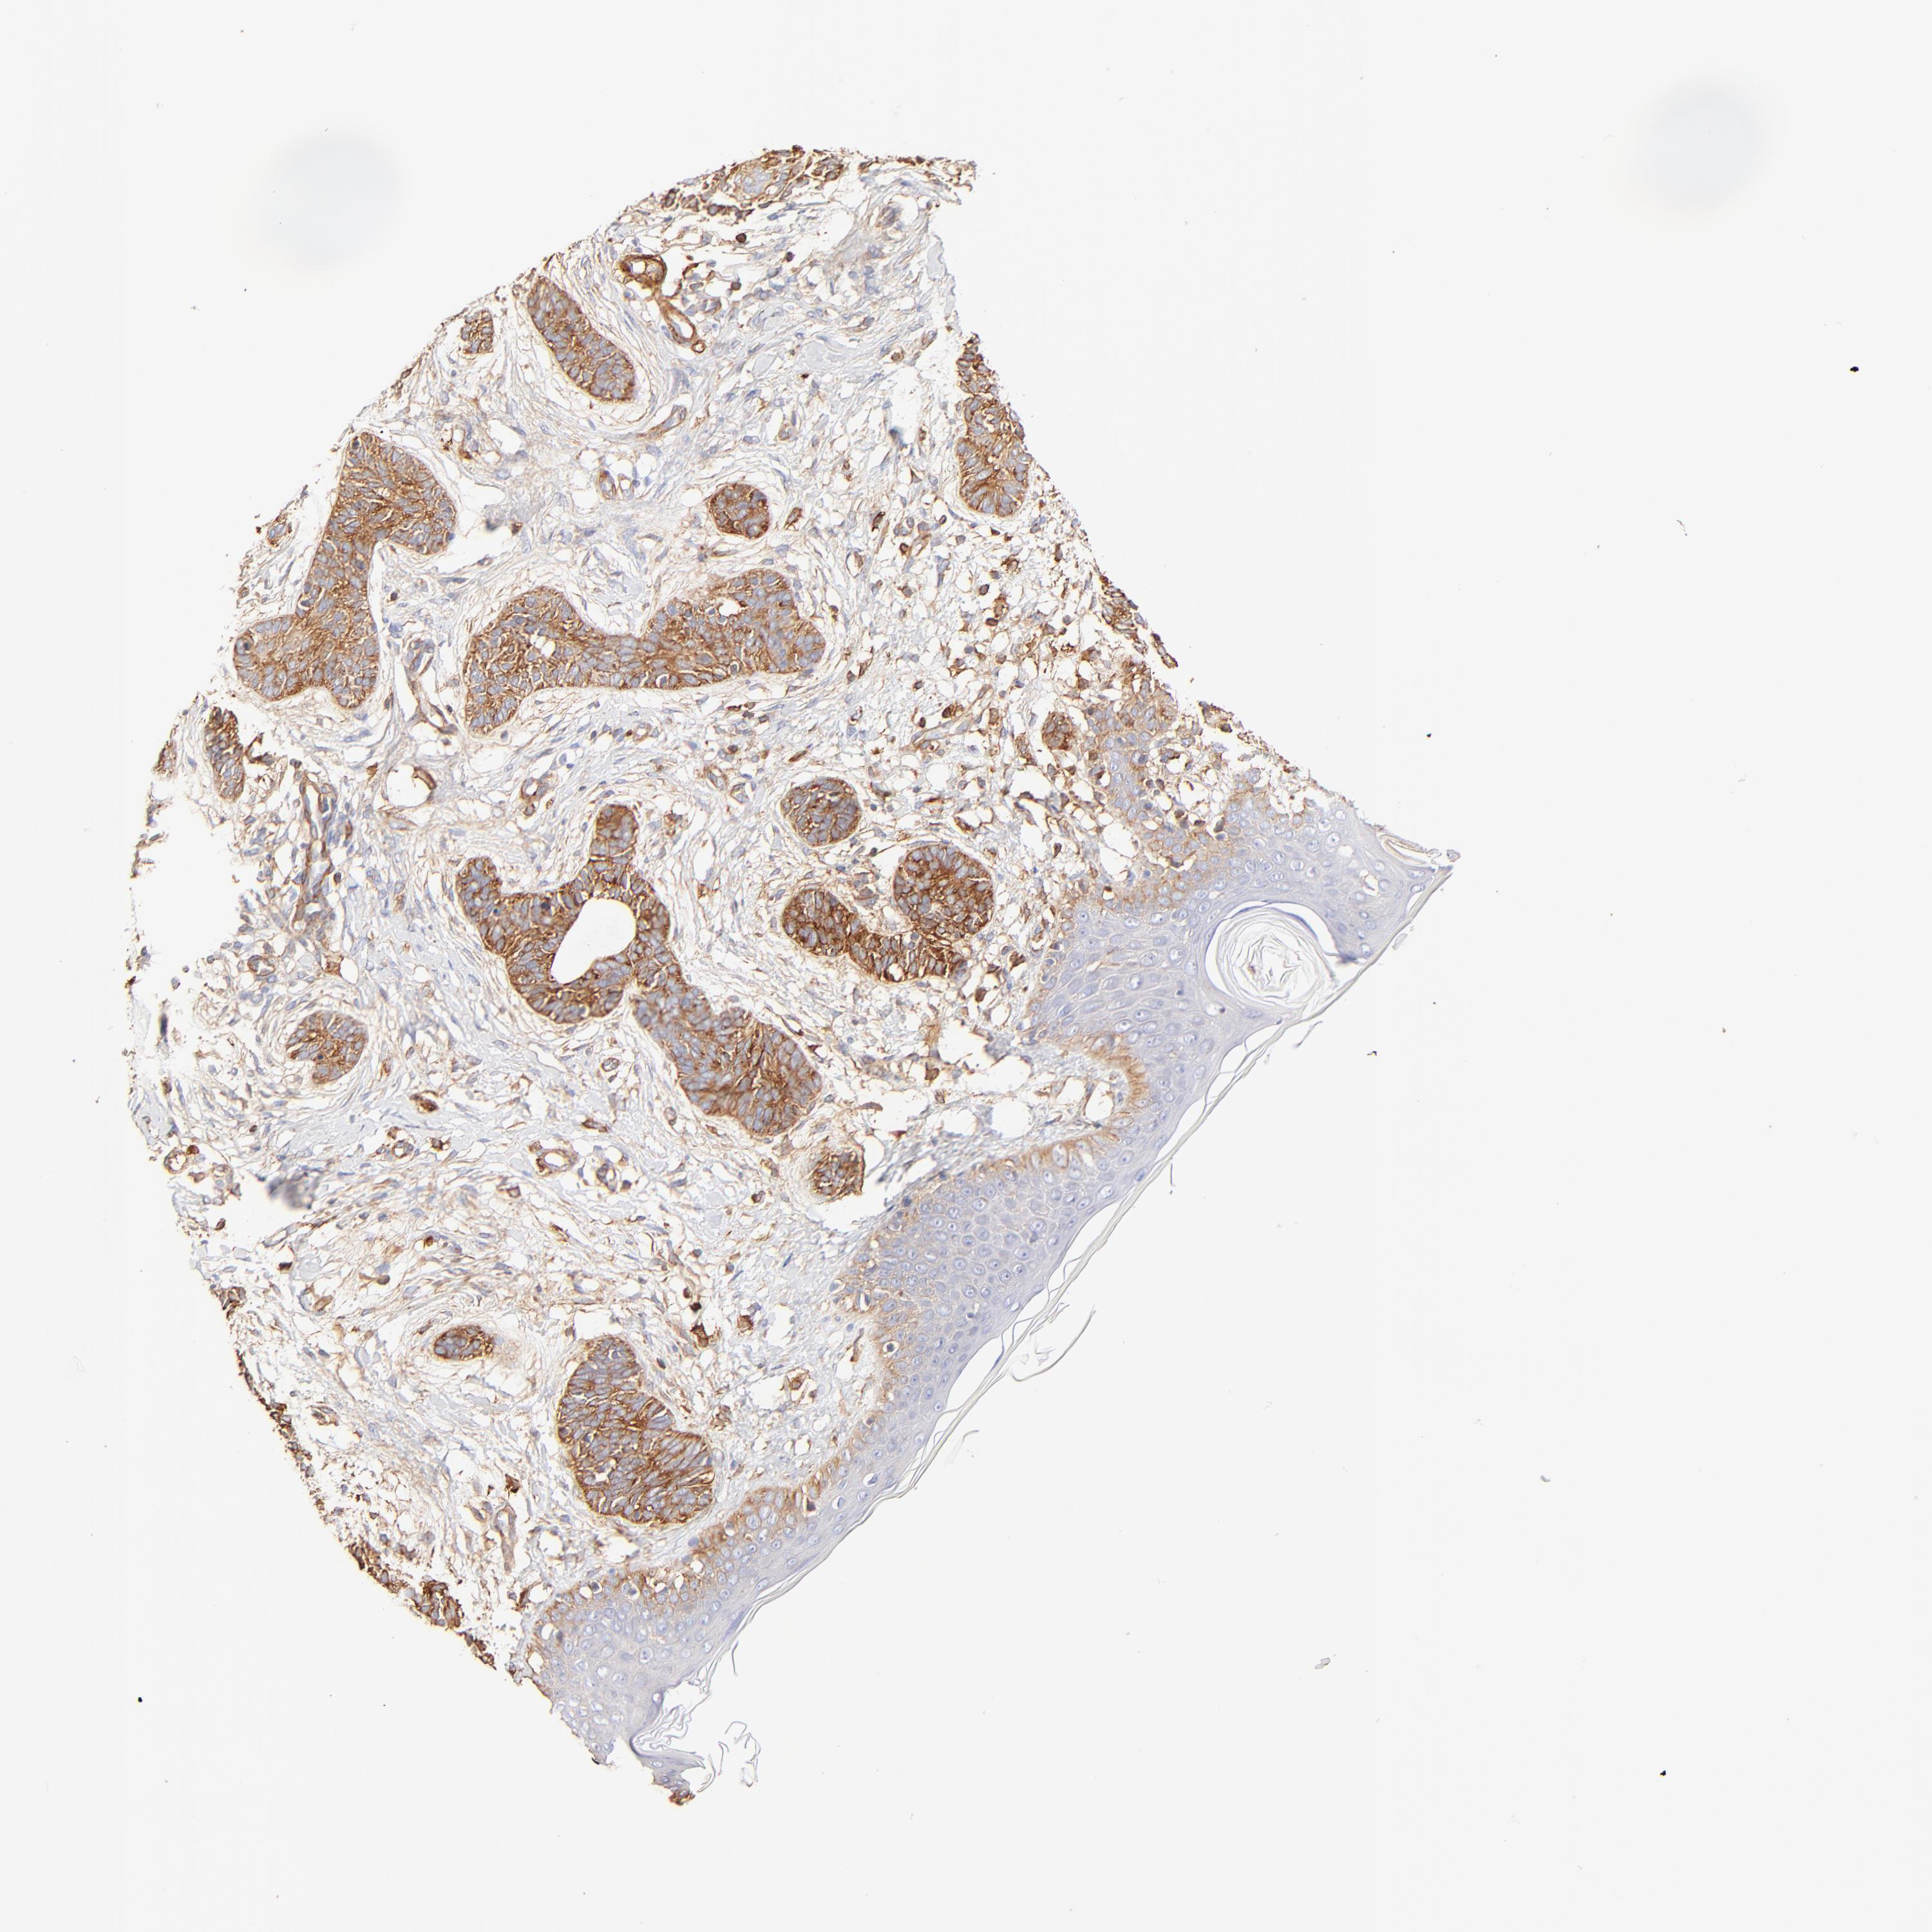

SKIN CANCER - Protein expressioni

A mouse-over function shows sample information and annotation data. Click on an image to view it in a full screen mode. Samples can be filtered based on level of antibody staining by selecting one or several of the following categories: high, medium, low and not detected. The assay and annotation is described here.

Each image is clickable and will lead to virtual microscopy that enables deeper exploration of all samples and also displays staining intensity scores, fraction scores and subcellular localization as well as patient and tissue information for each sample.

Antibody HPA001115

Antibody HPA002925

Antibody CAB000356

Staining

High

Medium

Low

Not detected

Intensity

Strong

Moderate

Weak

Negative

Quantity

>75%

75%-25%

<25%

None

Location

Nuclear

Cytoplasmic/membranous

Cytoplasmic/membranous,nuclear

Squamous cell carcinoma, NOS

Basal cell carcinoma